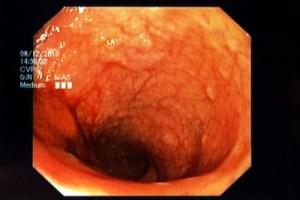

I walked to the dimly lit procedure room where the doctor showed me the 50-inch Vizio where he’d be inspecting my innards up close and personal.

When I woke up a little early, I saw what he was really doing – watching a PBS documentary on the Canyonlands. At least that’s what it looked like without my glasses.